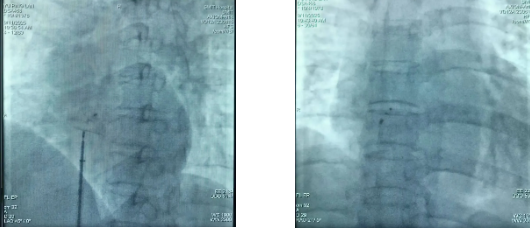

术后影像片

明确诊断后,考虑手术风险和难度高。面对这一复杂病例,市二医院副院长刘燕锋博士带领心血管内科医疗团队进行周密的术前讨论和充分准备,得到患者及家属同意后,为患者实施经导管卵圆孔未闭封堵术。手术过程顺利,仅用时30分钟。术后第二天,患者即可下地行走,现已康复出院。

据刘燕锋博士介绍,卵圆孔未闭封堵术是微创手术,具有显著的技术优势,与传统手术相比,微创方式创伤小,能有效减少患者术中及术后的痛苦,同时恢复速度快,大大缩短了患者的住院时间,且安全性高,有效降低了手术并发症的发生风险。